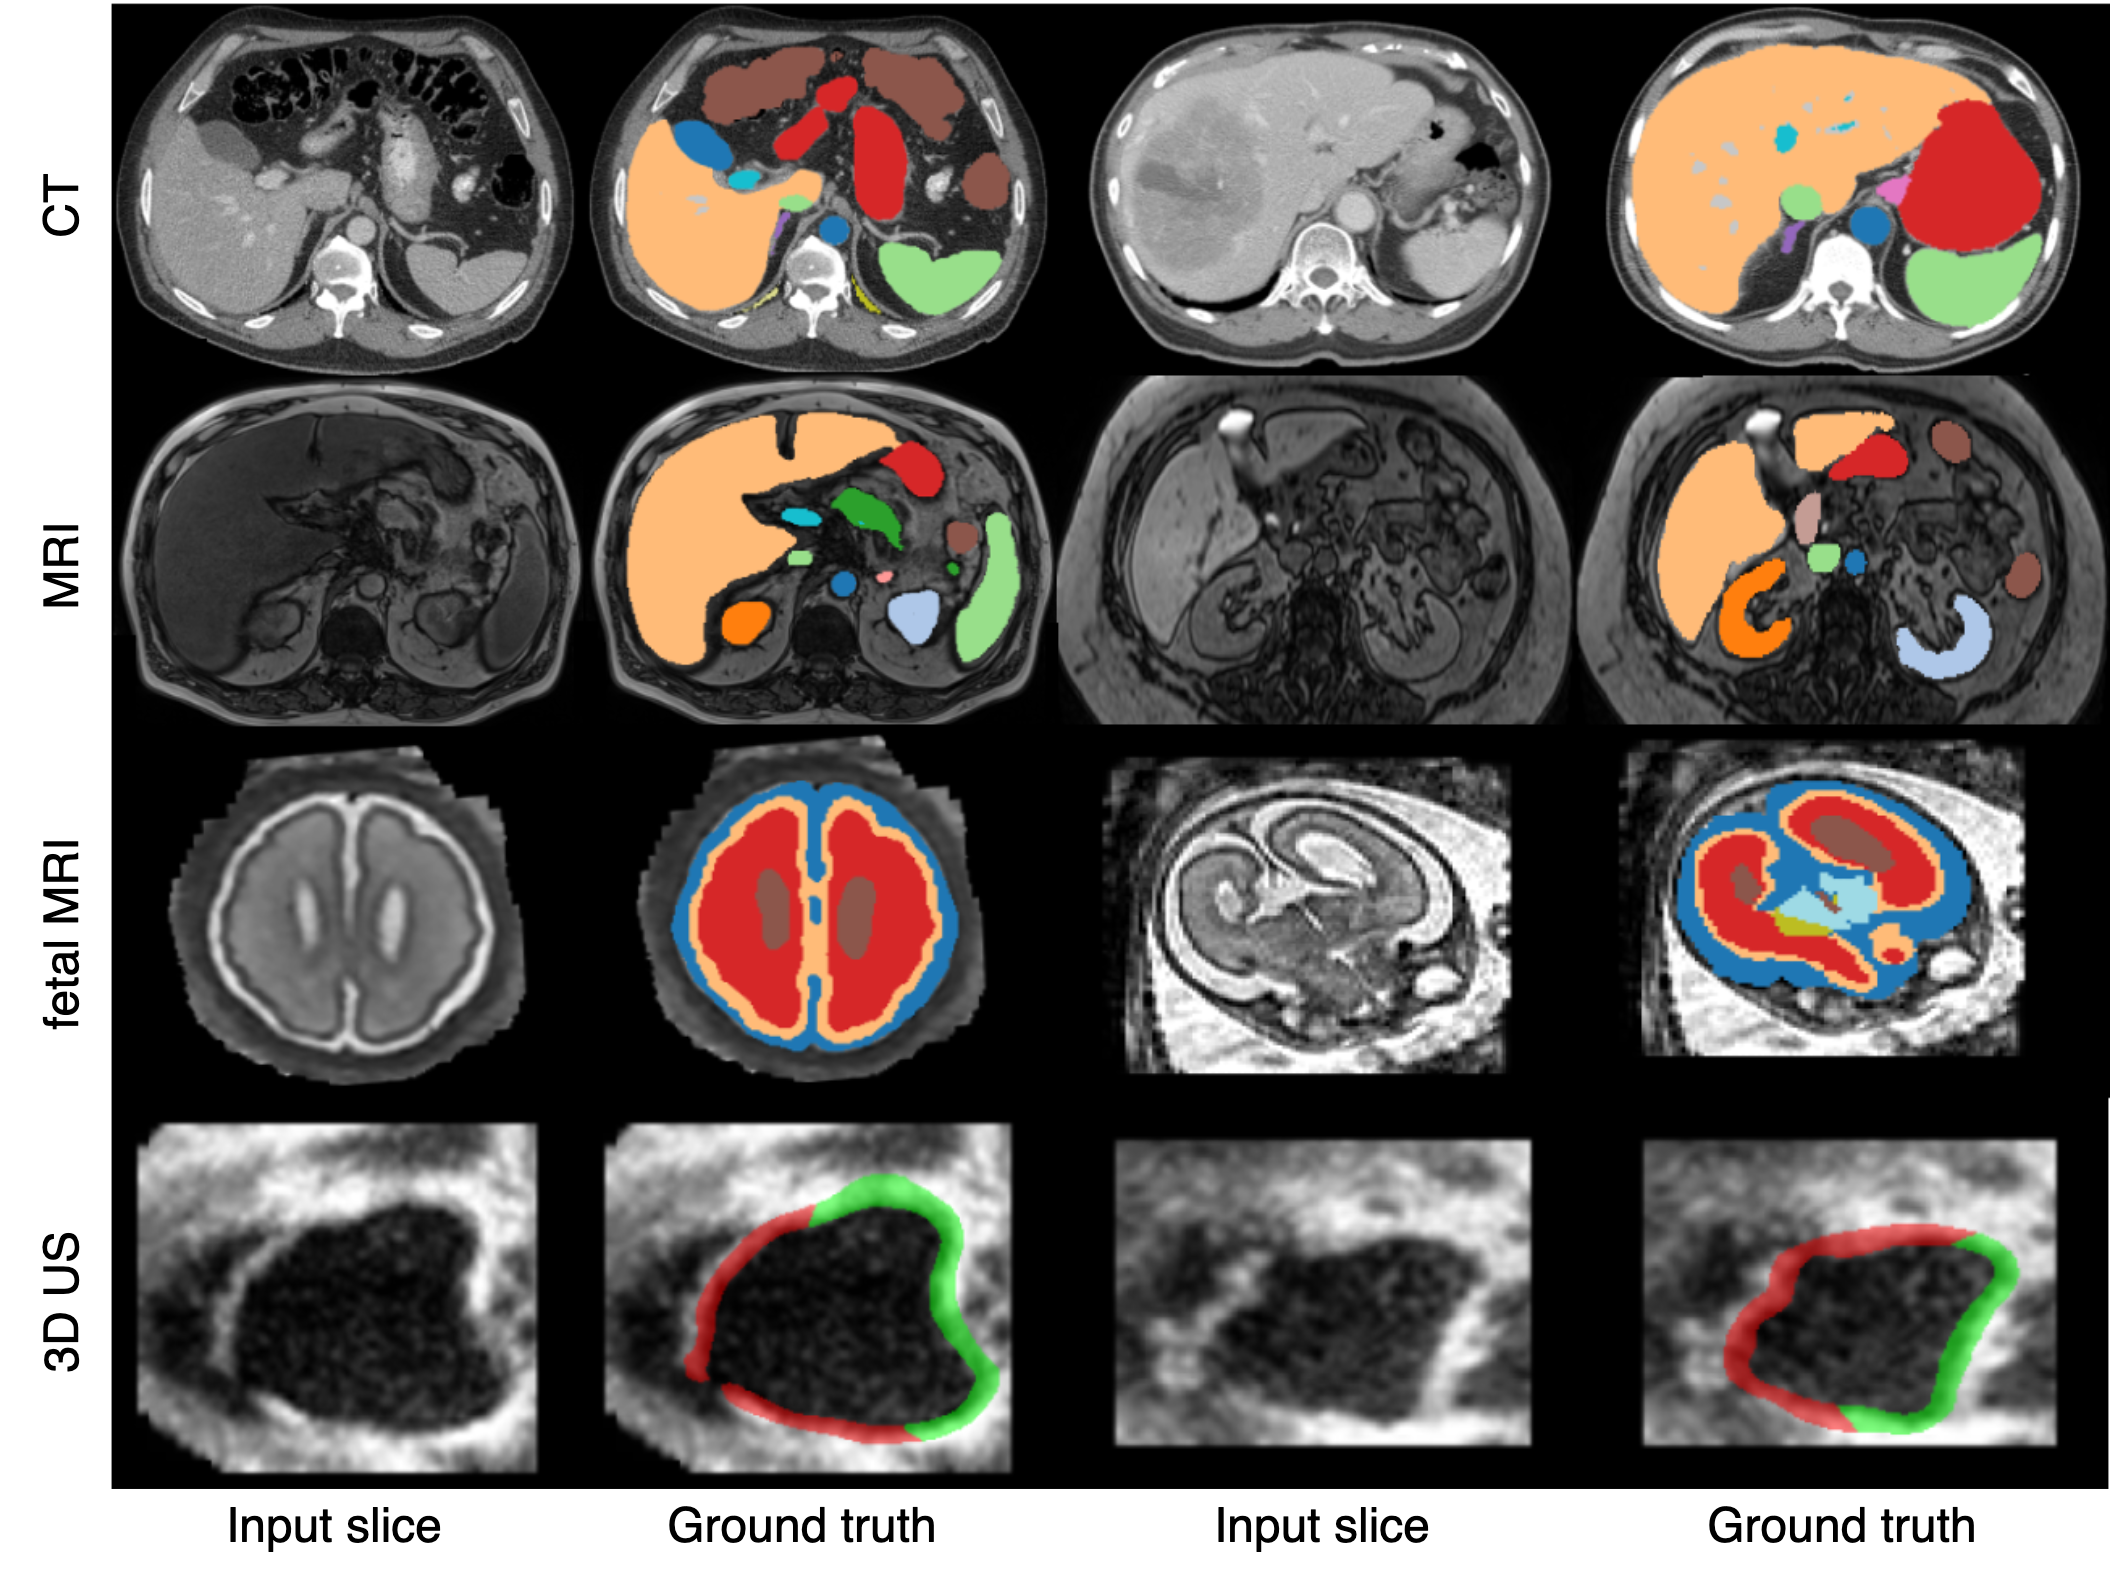

Qualitative results. Figure 2 presents a qualitative comparison of our proposed Mamba-HoME method against the five top-performing baselines across three primary 3D medical imaging modalities: CT, MRI, and US. These modalities exhibit different organ contrasts, noise levels, and resolutions. Mamba-HoME demonstrates consistent improvements in segmentation quality across these scenarios. In the first row, it effectively handles small and closely located structures, showing precise boundary delineation while reducing common artifacts seen in baseline predictions. The second row highlights its capability to accurately segment organs of various shapes and sizes, even under low image quality conditions, with reduced susceptibility to over- or under-segmentation. The third row illustrates Mamba-HoME’s robustness in handling noisy and low-resolution data, maintaining clear and anatomically accurate boundaries.

Figure 2: Qualitative segmentation results from top to bottom: CT, MRI, and 3D US. From left to right, each column shows the input slice, ground truth, the proposed Mamba-HoME, and the five next best-performing methods.